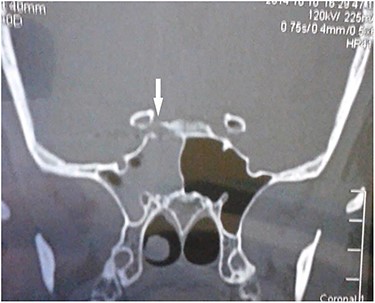

CT scan coronal view showing gun pellets near the right cavernous carotid artery (arrows).

CT scan coronal view showing right sphenoid sinus opacification with denudation of sphenoid sinus wall (arrow).